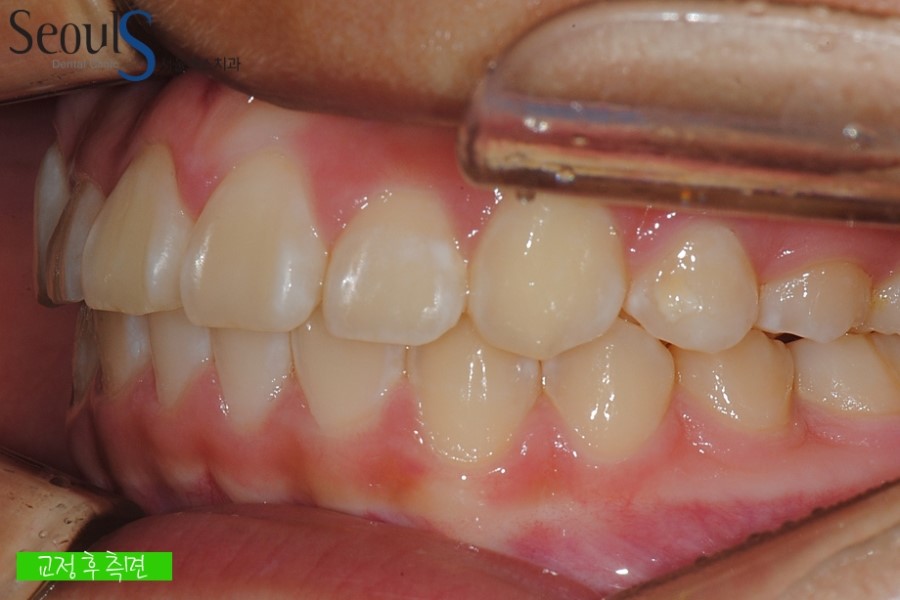

교정 후 측면 모습입니다

측면 역시 고르지 못했는데

예쁘게 교정된 모습입니다

측면 교정 전후 모습입니다